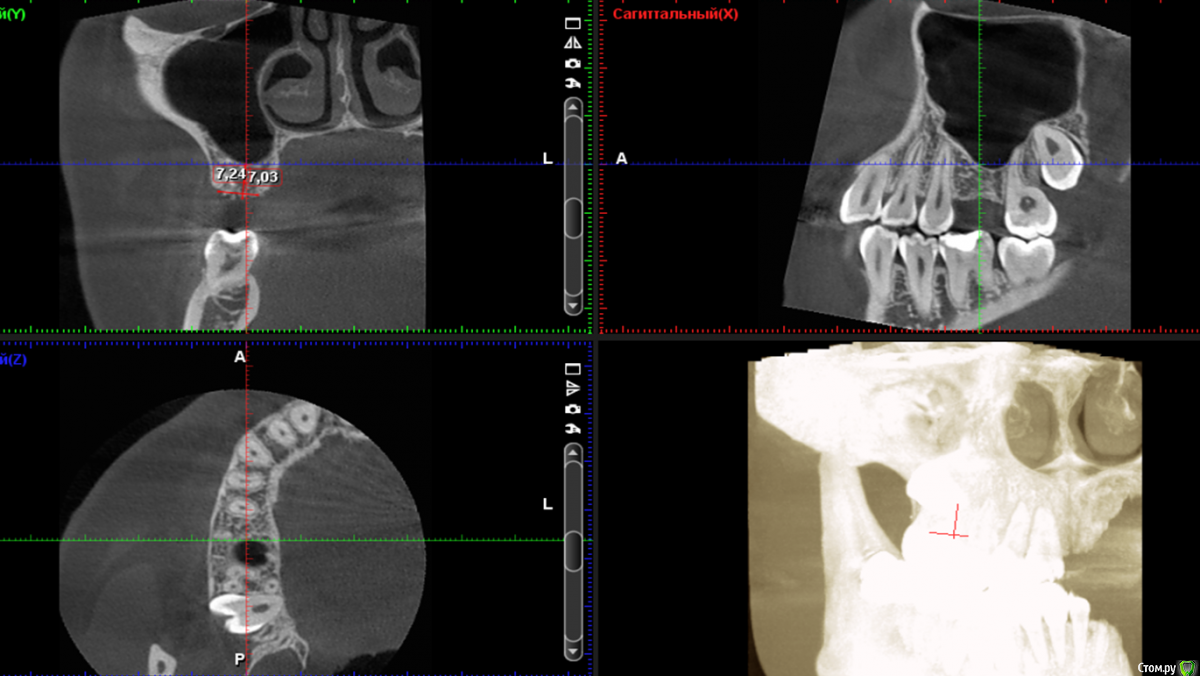

diesel87 Опубликовано 24 ноября, 2015 Поделиться Опубликовано 24 ноября, 2015 Спрошу у терапевтов, сегодня пришла пациентка полечить пульпит в 14, полечили, принесла с собой орто, посмотрел, забавная гранулема в пазухе выросла, причина видимо 16, есть подвижность 1 степени, со стороны неба отмечает периодические выбухания, которые сами проходят. Думаю ей 12 лет, не пациентке. Что скажите господа, эндо имеет смысл? http://fs5.directupload.net/images/151124/2hrfb9kp.jpg http://fs5.directupload.net/images/151124/nf6tk9pj.jpg Ссылка на комментарий

Л Ю С Я Опубликовано 24 ноября, 2015 Поделиться Опубликовано 24 ноября, 2015 Надо кт, может и не связано с зубом Ссылка на комментарий

Neilrus Опубликовано 24 ноября, 2015 Поделиться Опубликовано 24 ноября, 2015 Эод может сделать чтобы понять связано или нет? Не увеен насчет того, что это можно через каналы лечить. Но я бы ради интереса попробовал, если от зуба пошло, конечно. Вот только небно немного напрягает, резорбция стенки мощная. Ссылка на комментарий

DmitrySH Опубликовано 24 ноября, 2015 Поделиться Опубликовано 24 ноября, 2015 КТ надо бы, делать эндо, но в голове держать план возможной хирургической реабилитации.14, тоже гранулема. 1 Ссылка на комментарий

Л Ю С Я Опубликовано 26 ноября, 2015 Поделиться Опубликовано 26 ноября, 2015 Так что думаете коллеги, эндо или сначала к ЛОРикам?Сначала кт Ссылка на комментарий